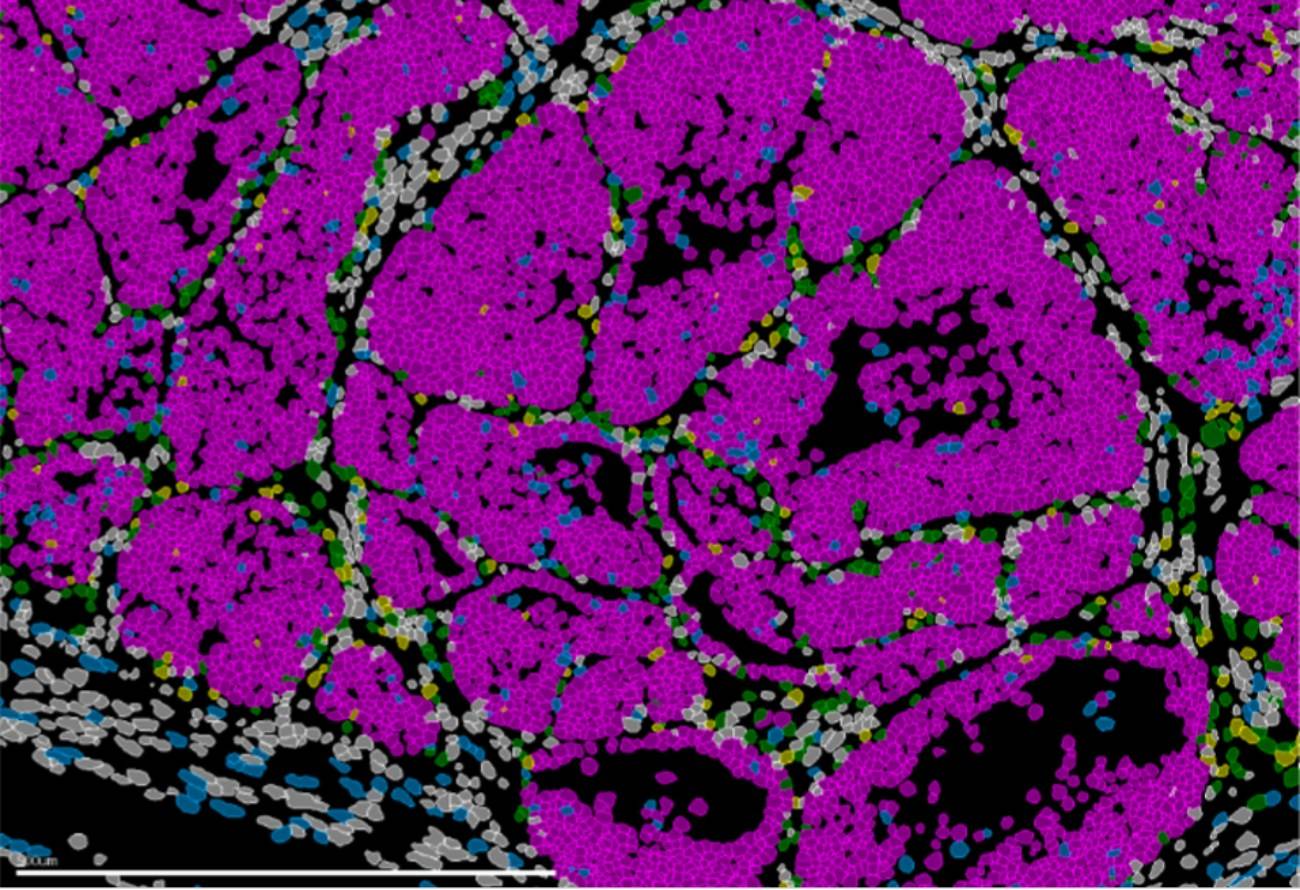

Para llegar a estas conclusiones, el equipo combinó modelos genéticos en ratón, análisis de célula única, estudios de cromatina y técnicas de transcriptómica espacial que permiten observar la organización y el comportamiento de las células directamente en el tejido tumoral. El procesamiento y análisis de los datos generados a partir de miles de células estuvo liderado por el experto en bioinformática del equipo de Nieto, el investigador Nitin Narwade.

A partir de un modelo de ratón y datos de pacientes, el trabajo publicado en Nature Communications muestra una población de células en el borde invasivo del tumor capaz de invadir y dividirse o de entrar en letargo. El gen Prrx1 es el encargado de regular este equilibrio, que determina la formación de nuevos focos tumorales en otros órganos, las temidas metástasis.

Este nuevo estudio desarrollado por el laboratorio de Plasticidad Celular en Desarrollo y Enfermedad, dirigido por Ángela Nieto, demuestra que la capacidad metastática no surge por azar ni depende únicamente del microambiente del órgano de destino. Por el contrario, el potencial metastásico ya está determinado en un conjunto de células presentes en el tumor que origina el cáncer. Estas células adoptan un estado altamente metastásico coordinado por un factor clave: el gen Prrx1.